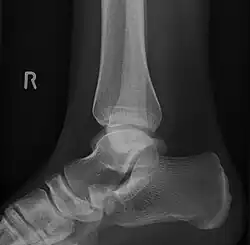

Projection latérale de type 2

Type 2